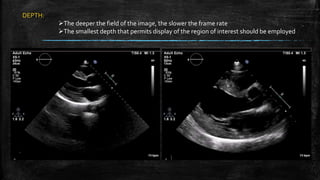

DEPTH:

The deeper the field of the image, the slower the frame rate

The smallest depth that permits display of the region of interest should be employed